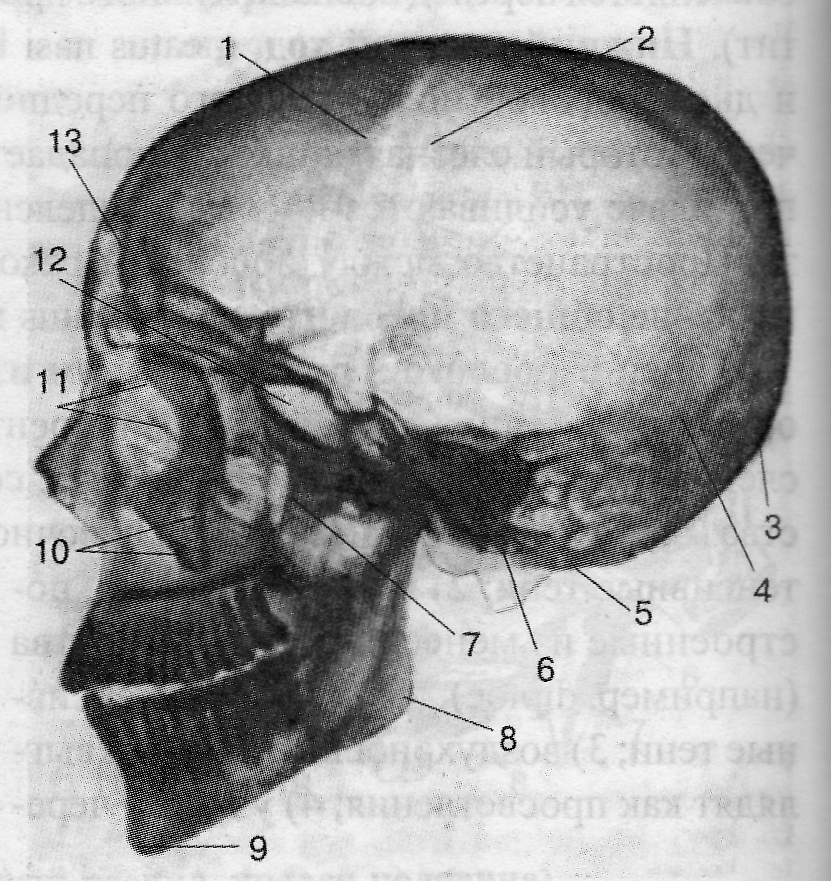

На рентгенограмме черепа в прямой проекции прежде всего необходимо обратить внимание на структуры, формирующие глазницы, полость носа, анатомические образования в области верхней челюсти, оцениваются форма, размеры и характер лобной и верхнечелюстной пазух, а также большое затылочное отверстие. На рентгенограмме в боковой проекции можно оценить черепные ямки, толщину и рельеф костей мозгового черепа. Особое внимание необходимо обратить на размеры и форму турецкого седла, клиновидной и лобной пазух. Оценка формы и размеров турецкого седла позволяет судить о его содержимом – гипофизе.

Рис. 3.32. Рентгенограмма черепа взрослого человека; боковая проекция.

1 – os frontale; 2 – sut. coronalis; 3 – protuberantia occipitalis externa; 4 – sut. Lambdoidea; 5 – processus mastoideus; 6 – condylus occipitalis; 7 – fossa pterygopalatina; 8 – angulus mandibulae; 9 – protuberantia mentalis; 10 – processus zygomaticus maxillae; 11 – labyrinthus ossis ethmoidalis; 12 – sinus sphenoidalis; 13 – sinus frontalis.